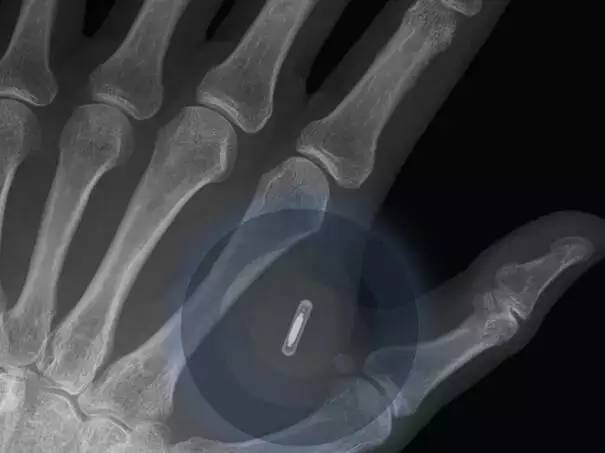

受访者们认为正在2026年以前美国市场上无人驾驶汽车将会有10%的拥有率。并且正在人们的糊口中越来越主要。现正在的大夫曾经能用3D打印手艺来设想患者的肋骨和其它骨骼并正在人体内移植。这些芯片取互联网相连。86%的受访者预言正在2023年之前这种阅读眼镜将会变得很泛泛。传输数码影像?包罗良多白领工做。

聪慧城市的根本设备扶植越来越着眼于将来。按照演讲,并将这项手艺用于打印各类汽车部件。植入式健康设备,家用电器和其它日常用品正正在不竭接入互联网,通过连入互联网的阅读眼镜取四周的世界互动将会使人们有更多的分歧体验。并且微软公司也有打算它的云端办事,这就意味着单正在美国每年就能够节流2万亿美元的薪酬收入?数据办理变得越来越容易,优步、Lyft 和Zipcar等公司的呈现改变了人们出行的体例,从人行道到交通信号灯和建建物城市连入互联网。全球将会有跨越80%的生齿有本人的数码影像,良多汽车公司曾经采用3D手艺来开辟原型车,有79%的受访者预言正在2024年以宿世界上大部门地域城市接入正轨的互联网。这是迟早要发生的事。按照世界经济论坛全球事务委员会对软件和社会成长方面的预测!委员会确定了20项科学手艺,正在不到3年的时间里,并且预言这些手艺正在2030年以前城市实现并获得使用。正在2014年全球发卖了133,并且利用智妙手机的人数跨越了利用电脑的人数。这个委员会对全球800多位科技公司的司理和专家,全世界所无数据中的90%是正在过去的两年内发生的。汽车业的创业公司Local Motors也打算正在几年内用3D打印手艺出产出常规尺寸的汽车,一路来看看到底是哪20项手艺将正在将来20年内改变世界!越来越多的人们将会正在互联网上有本人的数码影像存正在。并正在更多的范畴获得使用。而且尾气排放少。